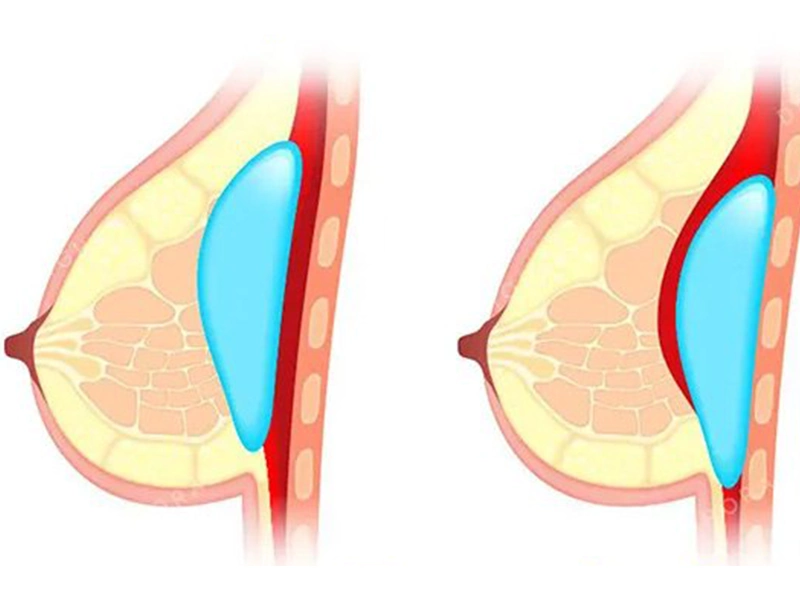

جابجایی پروتز سینه یکی از عوارض این جراحی زیبایی است. در چه مواردی رخ میدهد؟ پروتز سینه یکی از رایجترین